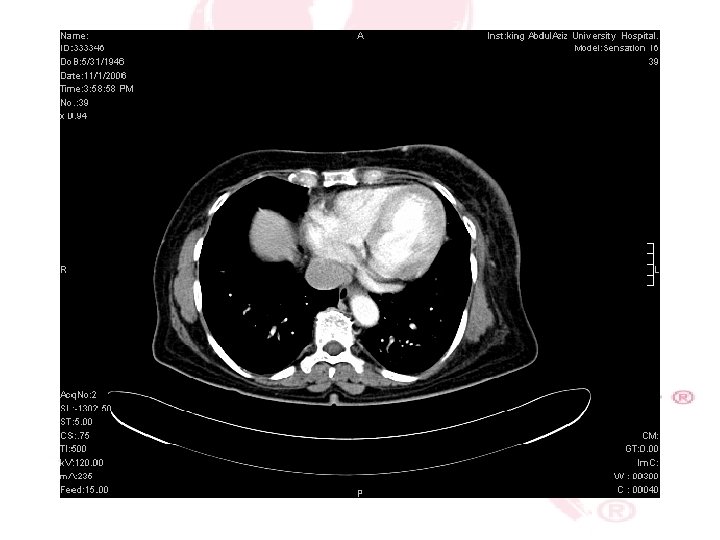

CT SCAN CHEST , ABDOMEN &PELVIS